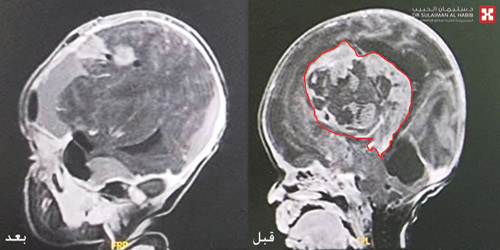

وقال الدكتور ناجي إن نتائج الفحوصات كشفت عن وجود ورم ضخم في الدماغ بطول (9×9) سم، متمركز بغرفة الدماغ الثالثة نتج عنه ضغط شديد على مراكز التنفس والقلب داخل المخ، وهو الأمر الذي يفسر الأعراض التي عانت منها الطفلة منذ لحظة ولادتها. وعلى الفور تم استدعاء استشاريي جراحة المخ والأعصاب والعناية المركزة وأطباء التخدير لمناقشة الحالة.

وأشار إلى أن الفريق الطبي بعد دراسة نتائج الفحوصات قرَّر التدخل العاجل لاستئصال الورم، وذلك للحيلولة دون إصابة الطفلة بمزيد من الأعراض الخطرة -لا سمح الله- وبعد اتخاذ كافة التدابير اللازمة لصحة وسلامة الطفلة، أجريت لها عملية جراحية معقدة استغرقت 4 ساعات تحت التخدير الكامل، مع الاستعانة بأجهزة الميكروسكوب المتطور ومراقبة الأعصاب، حيث تم تحرير الورم من التصاقاته واستئصاله بالكامل، وإزالة الضغط القائم على مراكز المخ الحساسة.